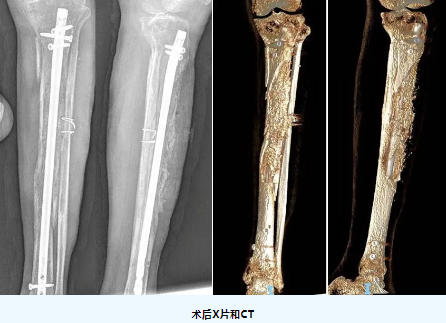

患者术后3个月再次入院,经创伤骨科副主任(主持工作)吴浩俊主任医师查看病人后,组织团队成员对该患者情况进行评估,最终决定对该患者实施了“外固定支架拆除、左胫骨骨水泥取出、胫骨骨折髓内钉内固定、自体骨和异体骨混合植入术”,现患者伤口愈合良好,肢体进行早期功能训练和康复治疗。